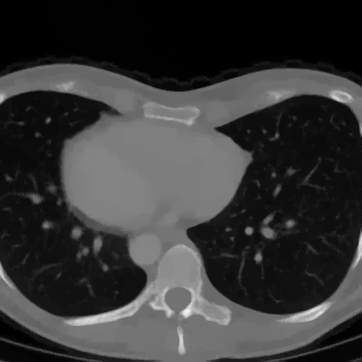

5.5.3 Results

In Figure 12 we compare the PD3O reconstructions (top) and their corresponding errors with respect to the ground truth (bottom) using different regularization parameter choices , and for PD3O. Obviously, using the estimated parameter-map leads to a significant improvement of the reconstruction. In particular, sharp edges are retained, while using a constant regularizing parameter results in a significant blur. This can be also seen in Table 4, where we compare the NRMSE, PSNR, SSIM and blur and evaluated on the first 100 test images of the LoDoBaP dataset. These results are visualized in Figure 13 using box-plots. Note that the FBP seems to better than PD3O- in terms of the blur effect, but this can be explained by the fact that FBP reconstructions admit a lot of high-frequency artefacts leading to a small blur effect.

Further PD3O- reconstructions with their corresponding estimated parameter-maps are shown in Figure 14. Note that the parameter-maps are given in a logarithmic scale. As expected, the regularization is strong in constant areas and less strong on edges or finer details in order to reduce a smoothing in these regions.